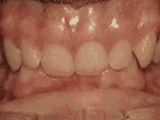

症状表现:牙齿缺失、牙周疾病等导致相邻牙齿无秩序前突。

症状表现:超出正常牙齿颗数,造成牙齿排列不齐,一般需要拔牙。

症状表现:牙齿过多,牙槽骨过窄,使牙齿没有足够空间生长就会造成牙齿排列不齐,需根据情况判断是否拔牙。

症状表现:通俗来讲就是咬牙时无法紧闭,上下牙齿中间有缝。

症状表现:上牙边沿覆盖下牙超过1/3,俗话说的天包地。

症状表现:疾病外因等造成的牙列稀疏,牙槽骨过长或牙齿缺失,导致排列太宽松,零零散散。

症状表现:下牙边沿覆盖上牙超过1/3,俗话说的地包天。